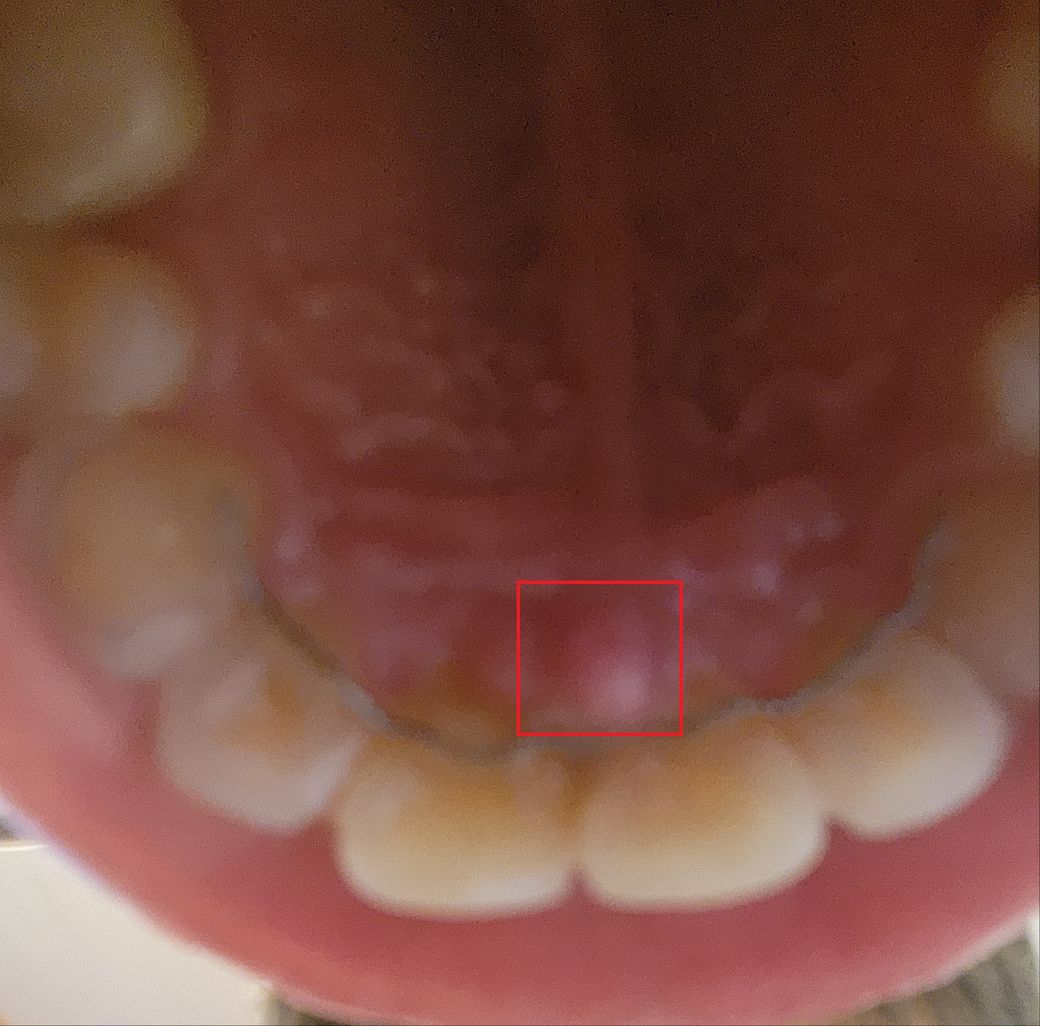

입천장 앞니 뒷쪽에 혹 같은게 있는데 무엇일까요

안녕하세요. 입천장쪽 앞니 바로 뒤에

작은 혹 같은게 몇일 전에 생겼고 통증이 있어 뜨거운 것을 먹기 힘듭니다.

일반적인 구내염은 이런 혹 양상은 아닌 것 같은데 그래도 구내염일까요?

사진의 화질이 좋지는 않지만 조언을 해주시면 감사드리겠습니다.

• 해당 부위는 이 입 천장에 있는 정상적인 구조물이기 때문에 큰 문제가 있지는 않습니다. 하지만 약간 도드라져서 나와 있기 때문에 자극이 된다면 불편감이 있을 수 있습니다. 구강 점막 조직이 자극이 되었을 경우에는 해당 부위를 자극하지 않는다면 대부분 일주일 이내에 통증이 줄어들게 됩니다. 자잔 확인을 위해서 치과에서 진료를 받아보는 것을 권유드립니다

• incisive papilla 부위이며 염증이 생긴 것 같습니다 자극적인음식, 매운음식 등에 의해 심화될 수 있으므로 자제해야 합니다 일반적인 염증 처치, 스케일링 및 구강위생관리로 치료가 가능합니다